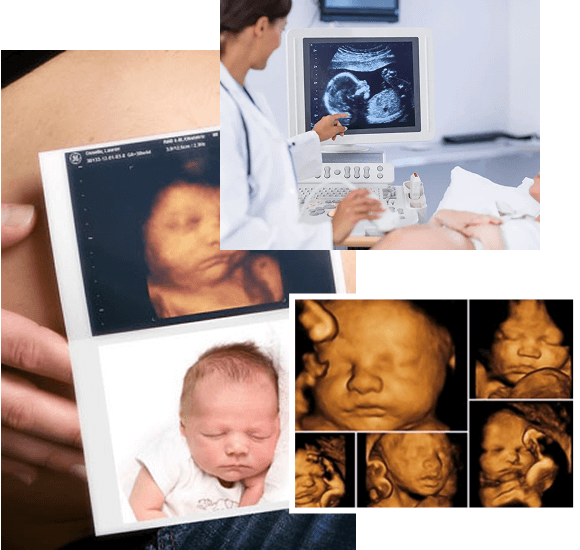

Ultrasonography is one of the most essential and non-invasive tools used for diagnosing and monitoring women’s health conditions. From early pregnancy scans to fertility-related monitoring and gynecological assessments, our facility offers trusted and accurate ultrasonography in Ahmedabad in a calm and professional environment.

Our diagnostic team ensures all scans are performed and reviewed by specialists with expertise in women’s health. We use advanced ultrasound machines that deliver high-resolution images with comfort and efficiency.